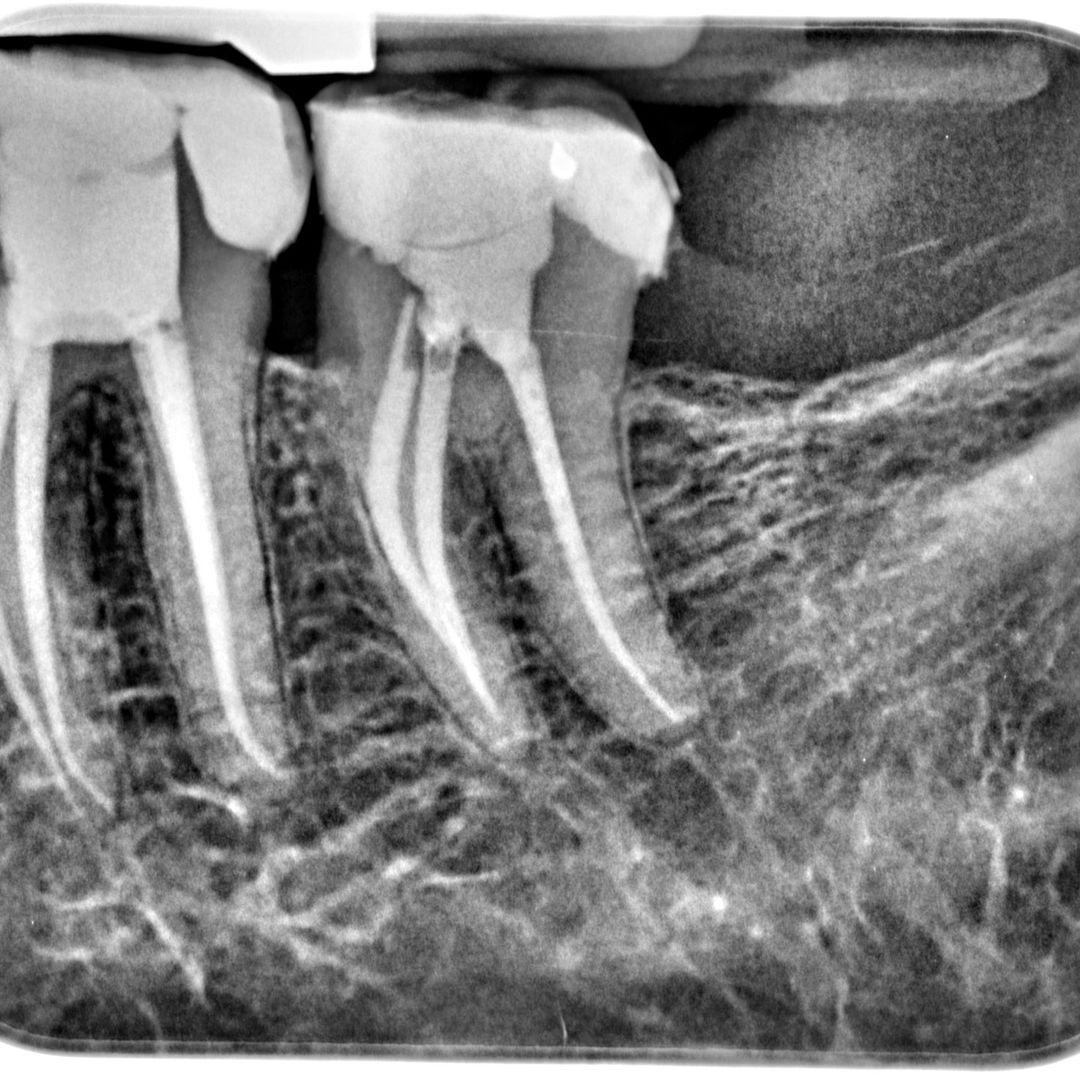

Root Canal Treatment

Root Canal Treatment is a procedure performed on the infected tooth to remove the decay affecting the pulp (underlying tissue containing blood vessels and nerve supply to a tooth). Simple filling procedure cannot restore a tooth’s dental health when the infection has encroached the pulp. Root canal therapy is the only alternative to save such tooth from being extracted. The main objective of root canal treatment is to preserve the infected existing natural tooth by disinfection. During a root canal therapy, access to the root canal present inside the root of a tooth is gained and the infected tissue is removed entirely. Hence Root Canal treatment bypasses extraction of the infected tooth and its replacement procedures thereby saving time and money.